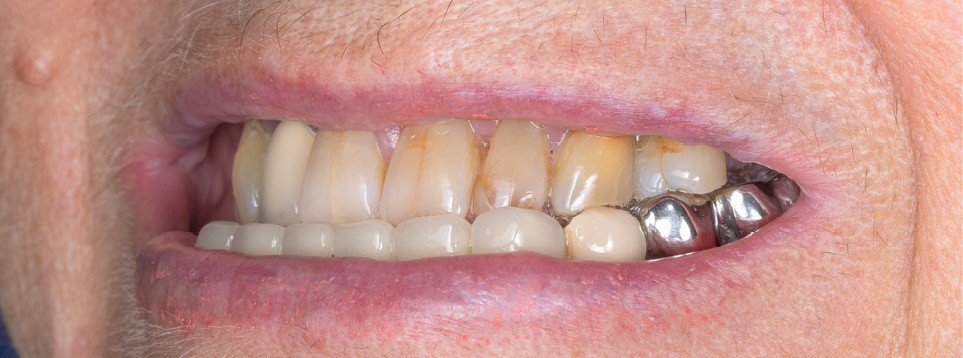

La première étape repose sur la récolte des données cliniques suivantes : – photographies exo- et endo-buccales (fig. 1), utilisées pour l’évaluation esthétique, le diagnostic initial et la communication avec le prothésiste ;